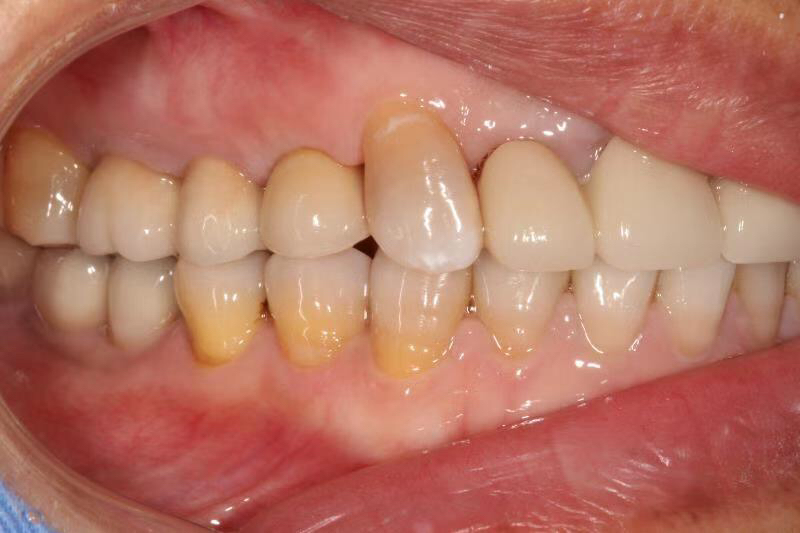

患者女,右上4号牙根管治疗后桩核冠修复,因进食硬物导致桩核冠脱落,未及时处理,导致残根无法修复,从CT上看,牙槽骨高度尚可,所以选择了即拔即种的治疗方案,且术中植骨盖膜、上愈合基台,为患者节省了就诊次数,提前了戴牙时间。